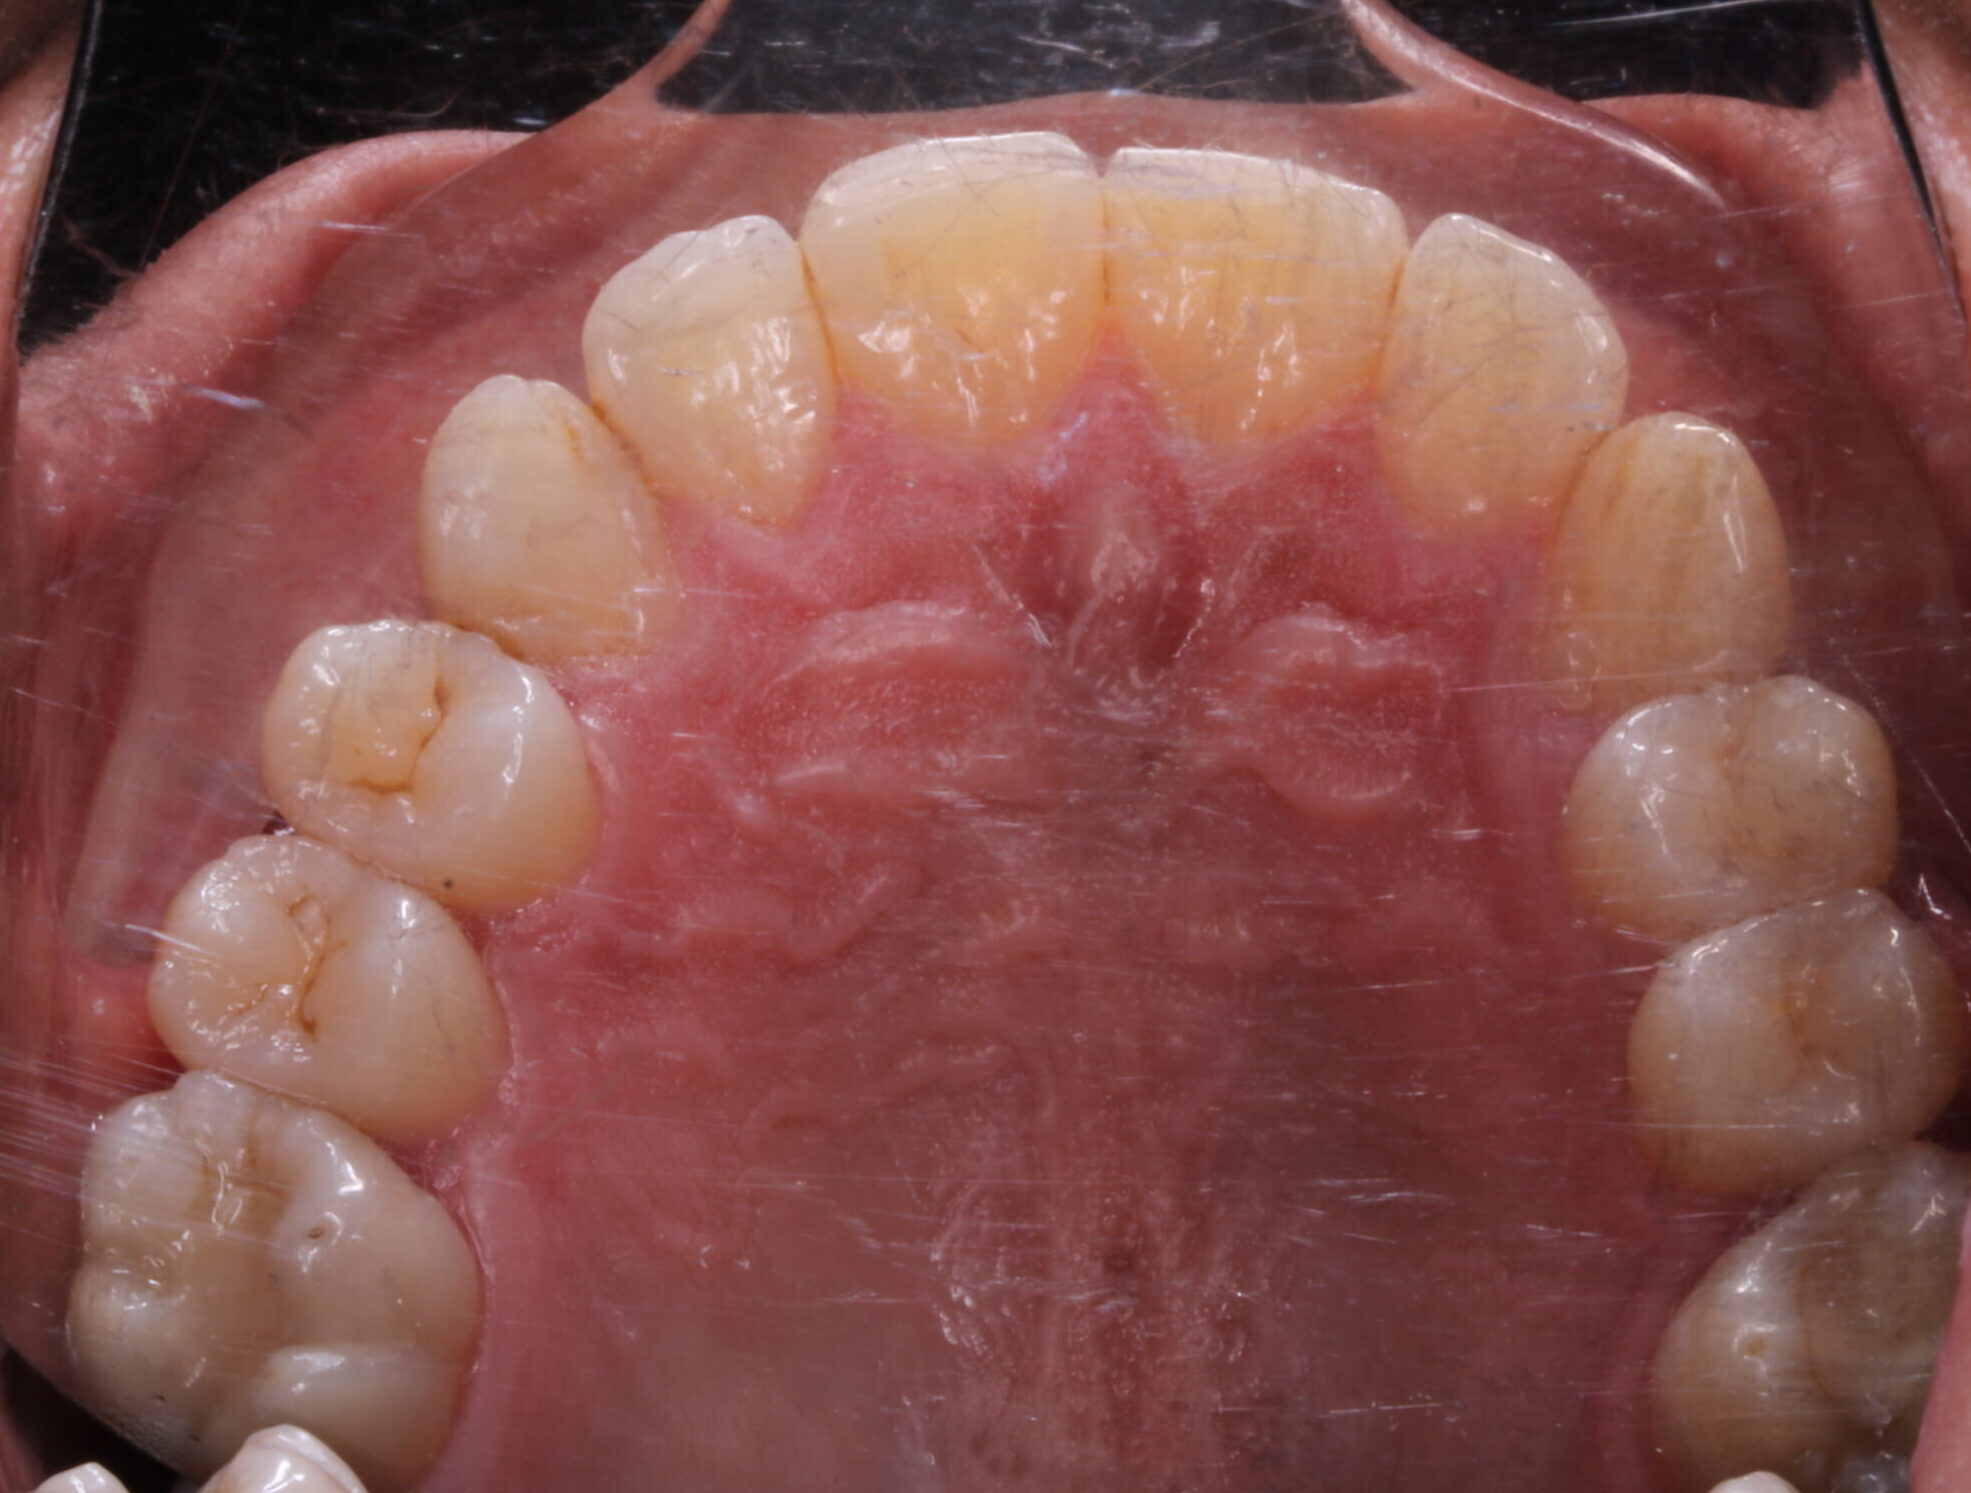

a) En la arcada superior: exodoncias de primeros premolares superiores( tamaño dental: 7,5mm) y uso de anclaje absoluto ( mediante dispositivos de anclaje esquelético), ya que la protrusión del incisivo superior era de 10,5 y la norma se sitúa en 4.

A eso hace referencia al número 7,5 de la parte superior y la flechita hacia atrás, que indica la retrusión que debemos hacer de los incisivos superiores. Dicho de otra manera el espacio que se obtiene de la exodoncias de 14 y 22, se consume al llevar los incisivos superiores hacia atrás. De ahí, el uso de microtornillos, para que los molares superiores no se mesializen.

B) En la arcada inferior: la situación es distinta, ya que el paciente, tiene ausencia de 34 y 44. Además  cursa con una desviación de la línea media inferior hacia la izquierda de 3mm. También, en el cuadrante 3, se ha consumido el espacio de dicha pieza ausente, por inclinación corono mesial de 36 y 37 por lo que nos vemos en la necesidad de recuperar ese espacio perdido. Al realizar el estudio, nos damos cuenta que la necesidad retrusión del incisivo inferior es 3,75. ( la norma es 1, y están en 4,7). Además analizamos, la curva de Spee, y para nivelarla necesitamos 0,75 por hemiarcada.

En el cuadrante IV, el espacio disponible de 7,5 se consume de la siguiente manera: centrado de la línea media(3mm), spee(0,75mm) y retrusión de incisivo inferior (3,7). Un total de 7,5 mm. De ahí, la necesidad de usar microtornillos en el cuadrante IV, para evitar la mesialización de los molares inferiores.

En el cuadrante III, no tenemos espacio, pero centrar la línea media, obtenemos 3mm. Por otro lado, perdemos 3,75 al retruir el incisivo inferior y 0,75mm por nivela spee, en un balance general de -1,5mm. Es por eso que en este cuadrante, es necesario enderezar 36 y 37, recuperar ese espacio perdido de 1,5mm, para que las cuentas salgan una vez más en la oficina.